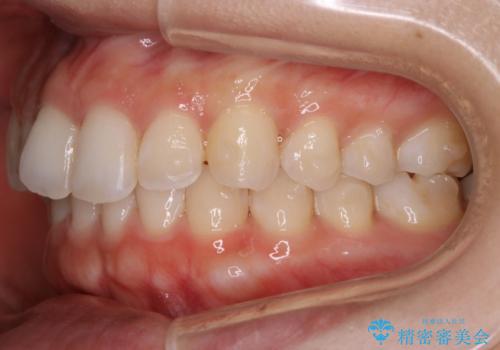

【非抜歯】下の前歯が1本少ない場合の矯正治療

- 前歯のガタつきを主訴に来院されました。

生まれつき下の前歯が1本少なく、その分のスペースを上の前歯がガタつくことで埋めているという状況でした。

上下それぞれのガタつきをとっていく過程で、歯1本分のスペースの差を、上顎の前歯のIPRで調整して並べる方法をご提案させていただきました。